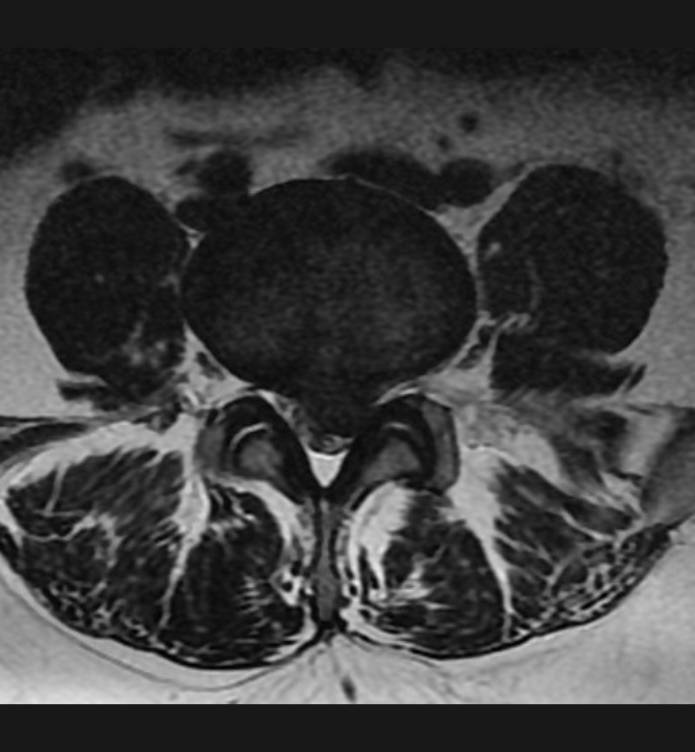

Basit Omurga ve Omurilik Anatomisi Omurga, 33 adet omur kemiğinden oluşur. Bu kemiklerin 7 tanesi boyun omuru, 12 tanesi sırt omuru, 5 tanesi bel omurudur. Beş tanesi birleşmiş olarak sakrum denilen kemiği ve 4 tanesi yine birleşmiş olarak koksiks denilen kuyruk sokumu kemiğini oluşturur. Omurganın görevi omuriliği korumak ve gövdeyi dik pozisyonda tutmak için destek […]